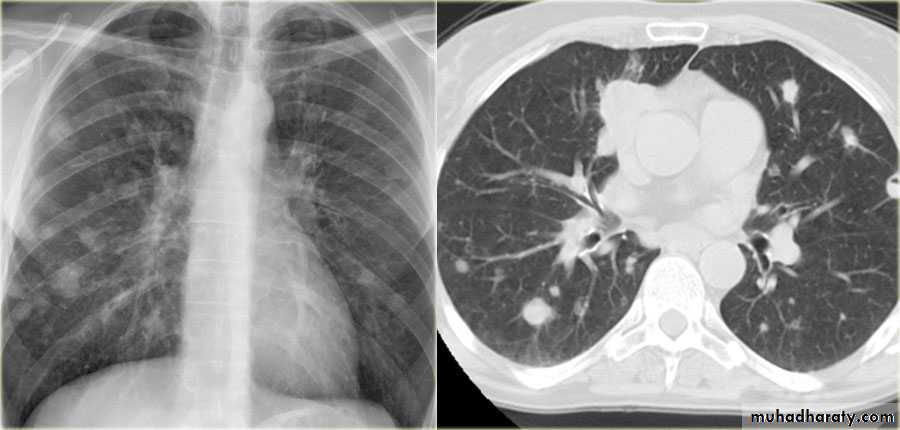

Secondary metastasis

!! ما شرحهم